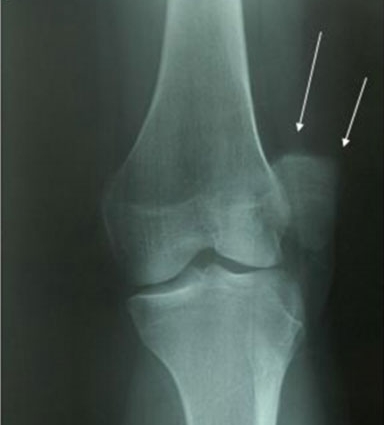

Вывих коленной чашечки требует обязательного лечения. Самостоятельное лечение строго запрещено, за исключением случаев неотложной помощи. Важно обратиться к врачу-травматологу, который назначит необходимые процедуры. Эффективность терапии во многом зависит от правильной диагностики. Для этого необходимо сделать рентгенографию коленного сустава, а при необходимости — томографию.

Для проверки правильности выполненных манипуляций проводится рентген. Иногда в процессе этой процедуры могут быть обнаружены костно-хрящевые обломки, которые не были видны на первоначальном рентгене.